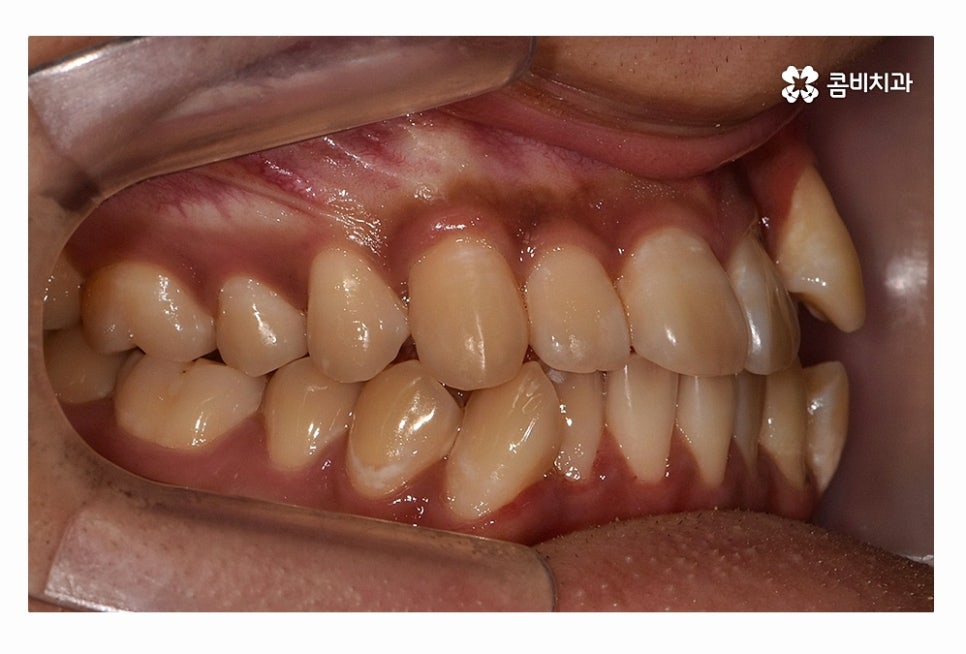

오늘 보시는 환자분의 사례처럼 덧니가 치아끼리 겹쳐 있는 경우에

치아의 이동 공간 확보를 위해서 덧니 발치 필요한 사례였으며

교합과 치아교정 후 얼굴 변화를 고려할 때도 치아교정 과정에서

발치가 필요한 사례였다고 볼 수 있어요.